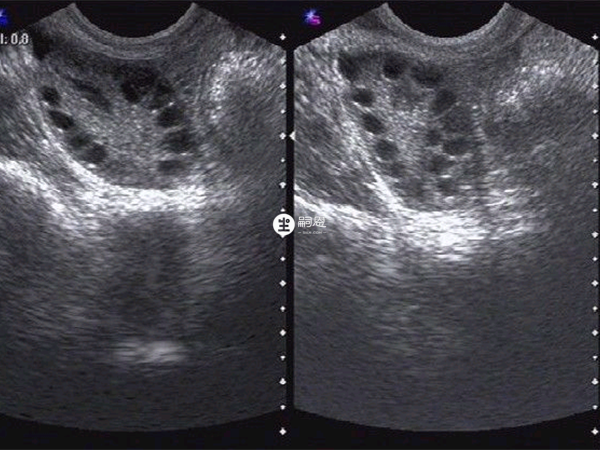

多囊卵巢不来月经不排卵,那些还没有长大的卵子通常不会形成显性卵泡,都还待在女性的卵巢内,或者部分形成了显性卵泡然后出现自行闭锁被身体消化吸收。一般多囊不来月经不排卵都是由于女性到了排卵期会有多个卵泡同时生长发育,而体内的激素水平并不能支持其都成熟,所以会出现不排卵的现象。而这些没有成熟的卵子因为没有长大,所以都还待在卵巢内或者被身体吸收。

囊卵巢综合征患者的内分泌特征主要是雄激素分泌过多,而高雄激素会抑制卵泡成熟,这样女性就不会有优势卵泡,自然就会诱发排卵障碍,甚至不来月经。而那些没有长大的卵子会停留在女性体内,部分成为显性卵泡后会自行闭锁然后被身体所吸收,还有部分优势卵泡会发生黄素化情况。